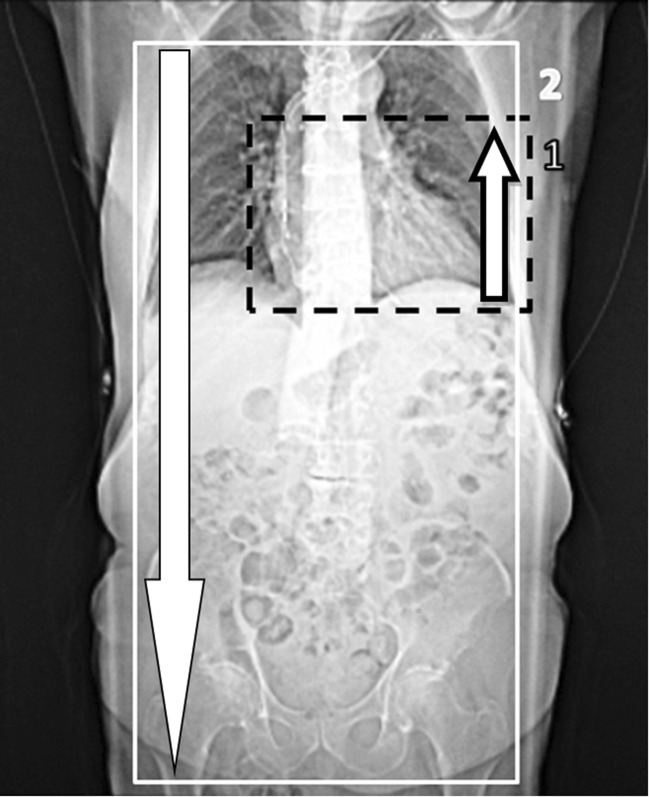

Directly afterwards, all patients received a non-ECG-triggered high-pitch spiral scan (flash) of the aorta in the cranio-caudal direction from the aortic arch to the femoral arteries (see Fig. 1). Scan parameters were as follows: reference tube-current-time product 400 mAsref; rotation time 0.28 s; slice collimation 128 × 0.6 mm; pitch value 3.0. Scan protocol varied for the two groups in tube voltage setting — group 1 at 70 kVp, group 2 at 80 kVp — and effective tube current was 90–122 mAseff (maximum possible values were 93 and 122 mAseff for 70 and 80 kVp, respectively). Images were reconstructed with individually adapted FOV at a 2-mm slice thickness with an increment of 1.4 mm using an I30f kernel (SAFIRE, strength 3; see Fig. 2). Dose modulation (CAREDose4D, Siemens) was used. In Table 1, all relevant scan parameters are summarized. The total scan time of the combined acquisition was 13–14 s: 6–7 s for retrospective ECG-gated acquisition, with a 5-s gap between acquisitions and 2 s for the high-pitch acquisition. In order to minimize the gap between acquisitions, the scan direction was adapted accordingly, starting with a caudo-cranial direction for the helical scan, followed by a cranio-caudal direction for the high-pitch spiral scan.

Fig. 1.

This figure shows the scout view with the planned anatomical range. The box with the dashed lines (1) indicates the retrospective ECG-gated acquisition of the heart in caudo-cranial direction. Box 2 indicates the high-pitch acquisition from the aortic arch to the femoral arteries in cranio-caudal direction